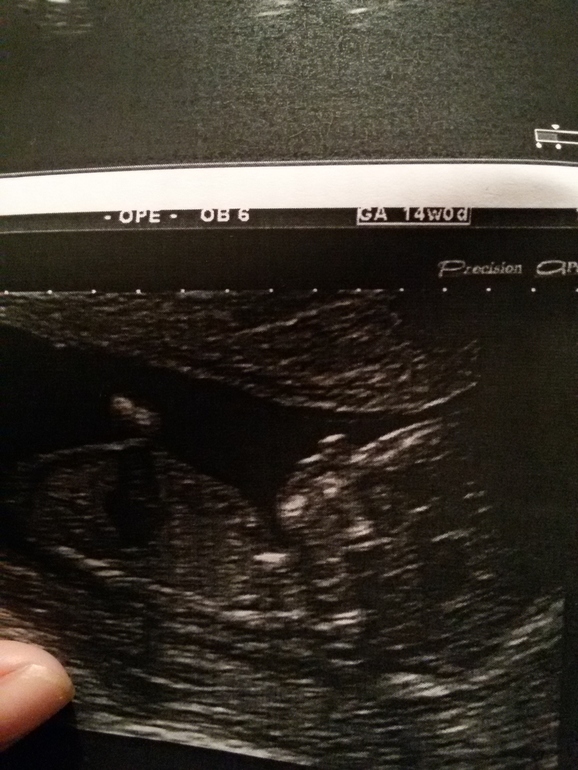

Сегодня сделал первое УЗИ!

Результаты: УЗИ, КТГ, доплера, скринингаПервое за беременность)Срок прям ровно 14 недель ,как и по менструации😊Плацента по передней стенке,что удивило)И у нас ДЕВОЧКА!!!Боже ,как же я рада,как же я её хотела)